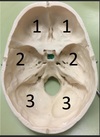

1. Identify the spaces labelled.

Anterior Cranial Fossa, Middle Cranial Fossa, Posterior Cranial Fossa